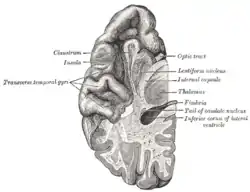

![]() Section of brain showing upper surface of temporal lobe. | |